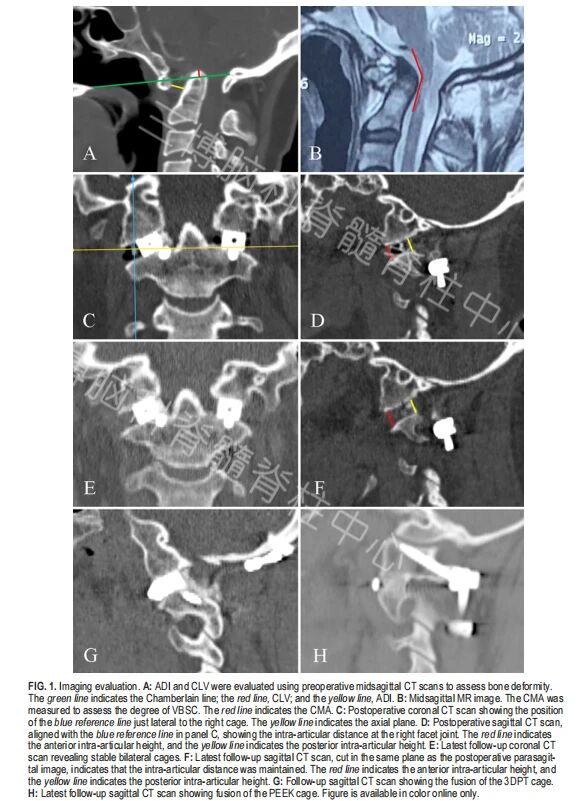

寰枢椎关节间撑开融合术包括关节间松解、撑开和植入融合器,常用于治疗颅颈交界区骨性畸形。关节间融合器用于C1-2 关节间融合已有20多年。然而,关于关节间融合器在随访过程中的转归却十分有限。本研究旨在报道C1-2 关节间融合器治疗颅颈交界区骨性畸形的随访效果。

本研究回顾性分析接受C1-2 关节间融合器植入术治疗颅颈交界区畸形患者的临床资料。观察测量融合器在术前、术后及随访时的正中矢状面参数。其他评估指标包括临床缓解情况、复位丢失、融合失败、融合器微动以及螺钉-棒系统失效。

以上的严重的并发症(完全脱出、全部陷入)少见,且与未融合相关。多数融合器未出现严重并发症,即相比于术后即刻的影像学资料,关节间融合器在术后至随访过程中有沉降的趋势,但是程度较轻微,且钉棒结构稳定,无松动、断裂迹象。